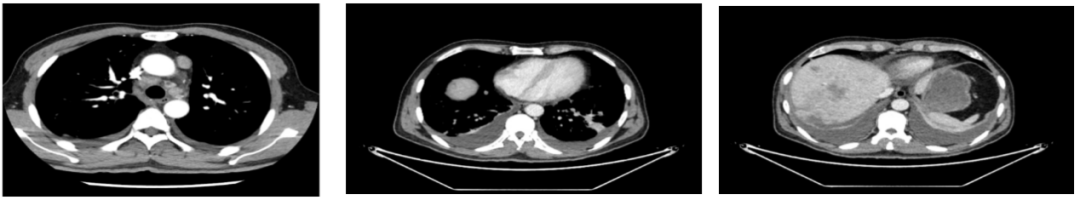

外院CT检查提示:1、两肺多发斑片状、结节影,性质待定,转移瘤?2、纵隔内多发肿大淋巴结;3、肝实质多发稍低密度影,性质待定(转移瘤可能性大)

2018-03-08 PET/CT示:胃癌(?)并全身多发淋巴结转移、肝脏多发转移、双肺上叶多发转移;

诊断:胃低分化腺癌合并肝、肺转移,并多发淋巴结转移HER2扩增